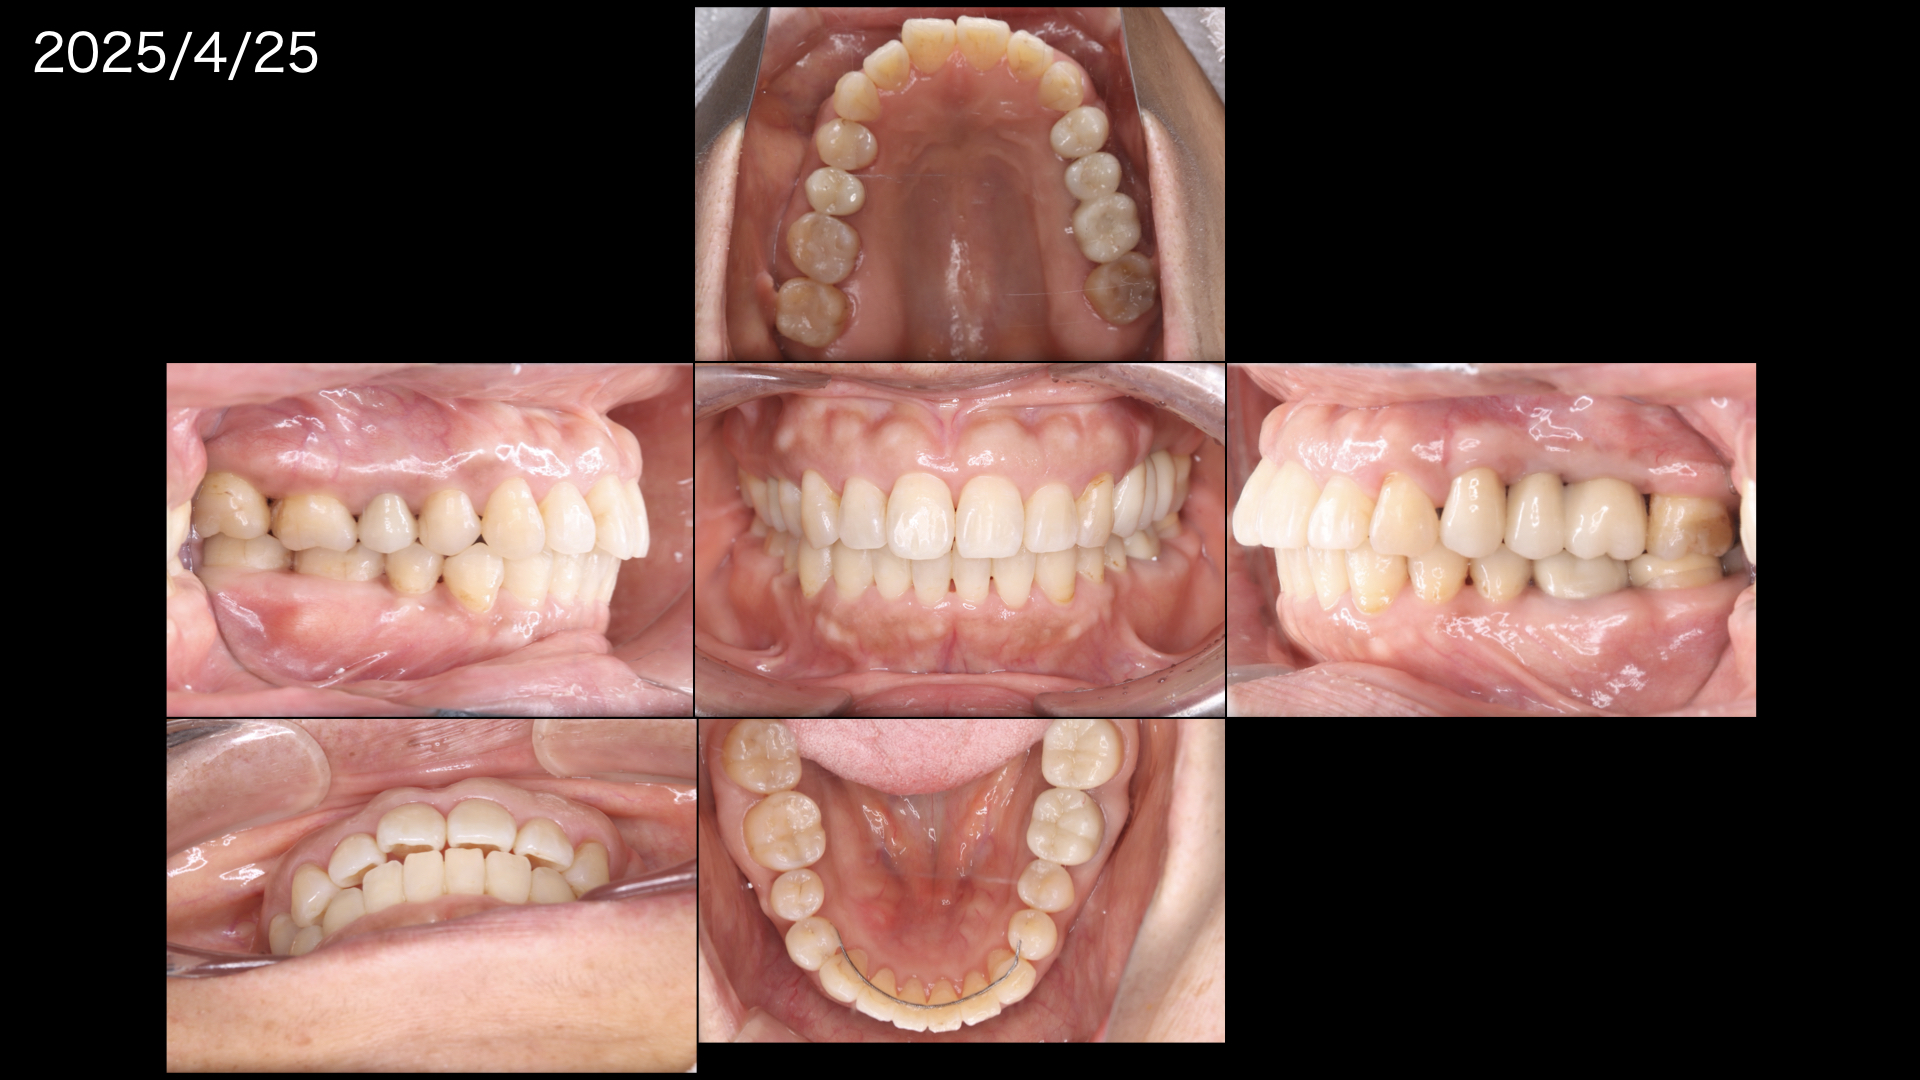

治療後の状態です。

前歯もしっかりと噛んでおりこれなら安心してインプラントを管理できます。

このように左側運動では左の犬歯(糸切り歯)だけが当たって、右側はあたらないように(離開:ディスクルージョン)

右側運動でも同じようになっており

治療前と違い、前歯が奥歯を守っている状態です。

やや歯周病が残っている歯はありますが、しっかりと今後もメインテナンスで経過をみていきます。